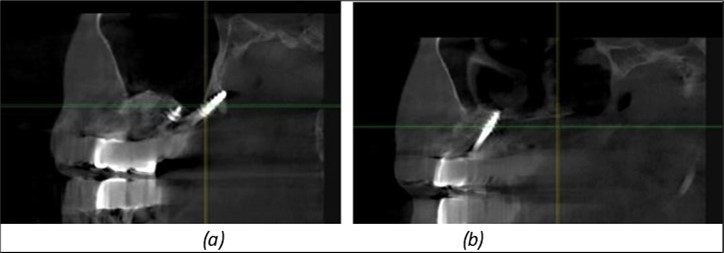

Figure 8.(a), (b) Sinus lift and grafting area with two stage implants before their removal. (c) area of fixation of BCS and TPG implants, avoiding the sinus lift and grafting area

Figure 9.Implants in the pterygoid plateau area: (a) TPG implant fixed in the maxillary-sphenoid junction area, quadrant 1; (b) TPG implant fixed in the maxillary-sphenoid junction area, quadrant 2.

Figure 10.Implants in the palatal sinus cortical area to avoid bone grafting: (a) BCS implant partially fixed in the graft material mass, partially in the palatal cortex; (b) Implant fixed in the palatal cortex at the junction with the nasal cortex, behind the graft material mass.